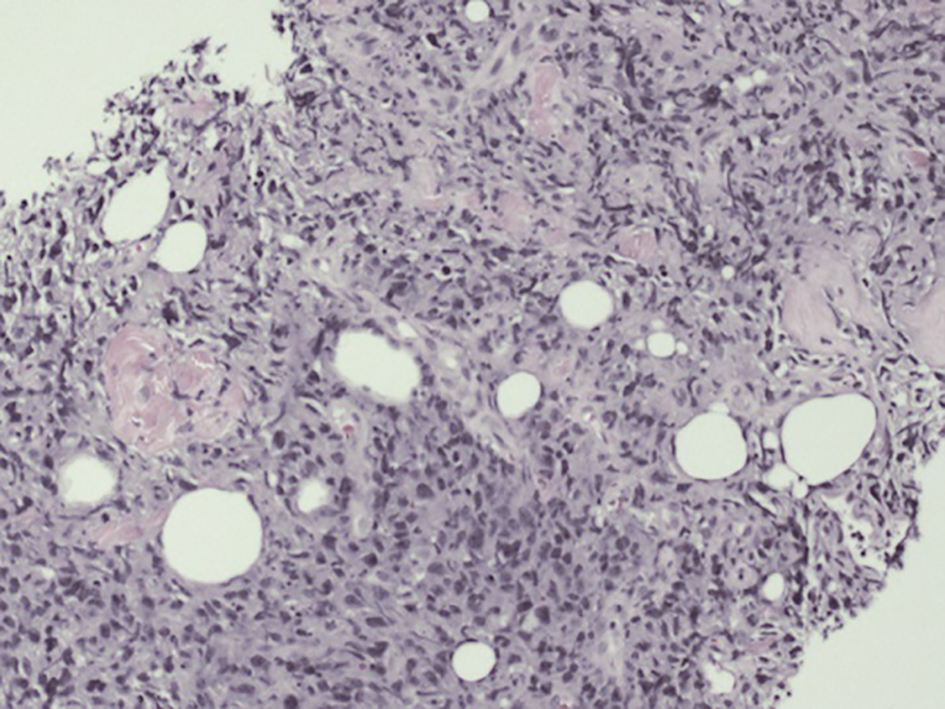

A 49-year-old man, current smoker, with past surgical history of cholecystectomy, presented with several weeks history of difficulty in urination, as well as dysuria, pelvic pain and occasional hematuria, with subjective fever. He had been treated with tamsulosin and finasteride as an outpatient with minimal relief. Due to persistent pelvic pain and obstructive uropathy, he was admitted to the hospital. On initial evaluation, patient was noticed to have mild suprapubic tenderness and no costovertebral angle tenderness or urethral discharge. Routine laboratory tests were within normal limits except hemoglobin 11.6, prostate-specific antigen (PSA) 0.4 ng/mL and lactate dehydrogenase (LDH) 347. Computerized tomography (CT) scan showed a 7 × 4 cm lobulated mass below the base of the bladder, possibly arising from the superior aspect of the prostate and invading the seminal vesicles. There was right pelvic/inguinal adenopathy with largest node measuring 2 cm posterior to the external iliac vessels and no evidence of distant metastatic disease (Fig. 1). This was further investigated by a prostate biopsy which revealed prostatic tissue with diffuse involvement of sheets of atypical cells with large irregular nuclei, prominent nucleoli numerous mitotic figures with immunohistochemical stains showing the tumor cells positive for CD45+, CD20+, BCL2+, MUM1+, while negative for CD10, BCL6, cyclin-D1, PSA, CK903, and P504S, consistent with diagnosis of a diffuse large B-cell lymphoma (DLBCL), activated B-cell type (Figs. 2 and 3). Bone marrow aspirate and biopsy were normal. Our patient was diagnosed with stage IIE bulky NHL of the prostate with low-intermediate risk group as per NCCN-IPI score. He had a normal echocardiogram and negative hepatitis panel. The patient was subsequently started on chemotherapy with R-CHOP (rituximab, cyclophosphamide, doxorubicin, vincristine and prednisone) regimen. Patient symptoms improved with chemotherapy. After completing six cycles of chemotherapy, patient had a positron emission tomography (PET) scan reporting no hypermetabolic disease and remains in remission and will be followed up closely.

![]() Click for large image | Figure 2. Prostate biopsy: low power view of the prostate core showing a diffuse proliferation of atypical pleomorphic cells. |

![]() Click for large image | Figure 3. Prostate biopsy: high power (× 40) view showing cellular pleomorphism and nuclear karyorrhexis. |